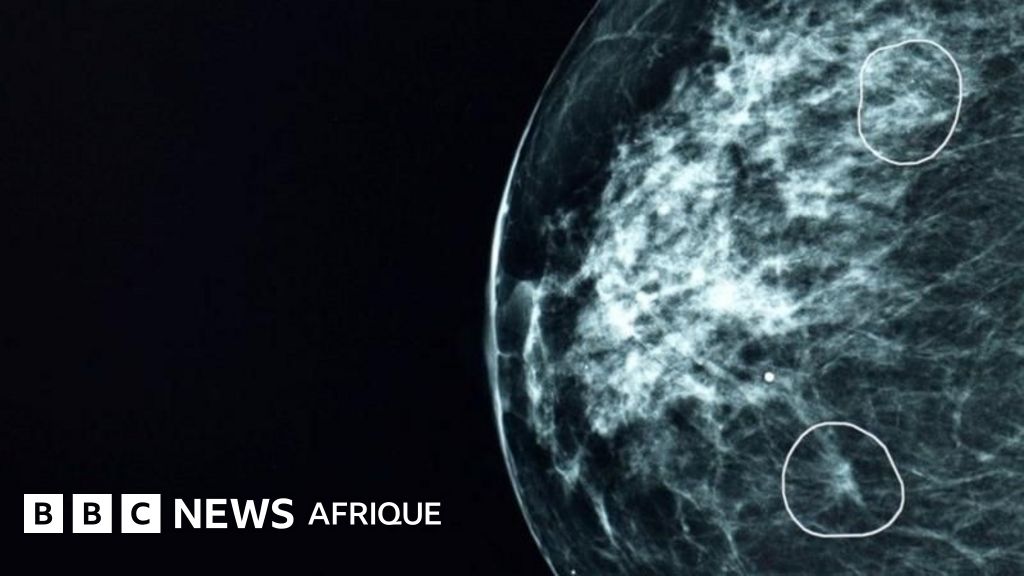

Dans le Parlons IA de la semaine 13, découvrez l’impact potentiel de l’IA sur la préservation de l’environnement. Explorez comment les technologies d’intelligence artificielle peuvent détecter des tumeurs cancéreuses que les médecins pourraient ne pas remarquer. Plongez-vous dans les opportunités offertes par l’IA dans le secteur de l’agroalimentaire.